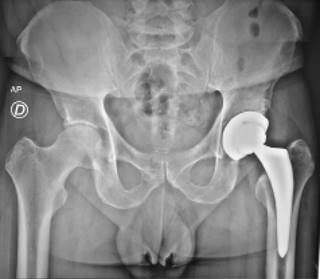

Se retira la tracción y se incrementa la rotación externa hasta llegar a 90 grados. En ocasiones es necesario practicar liberación secuenciada de la cápsula posterior, procurando incrementar la rotación externa a 120 grados empleando el posicionador, más la extensión máxima y aducción de 40 grados. Con el fin de evitar fracturarlo, es importante verificar que el trocánter mayor esté libre en posición lateral al borde acetabular, antes de iniciar la flexión. Una vez lograda la postura, se identifica el canal femoral y se inicia la preparación con raspas progresivas de diseño específico para abordaje anterior ya que tienen un offset predeterminado. Se colocan los componentes de prueba para cuello y cabeza. Con ayuda del posicionador de extremidad se efectúa la reducción, se verifica la estabilidad protésica y usando fluoroscopía se verifica la longitud de la misma y, una vez seleccionados los implantes definitivos, se realiza de nuevo luxación controlada del implante y con esos mismos movimientos se lleva la extremidad a la posición previa. Se sustituyen dichos componentes femorales de prueba por los definitivos (Figura 6). En la generalidad de los casos se utilizó un drenaje con reservorio por un mínimo de 24 horas. En todas esas incidencias se obtuvo una imagen radiográfica simple en proyección anteroposterior antes de mover al paciente de la mesa quirúrgica en la sala de operaciones (Figura 7).

Los enfermos fueron evaluados a los 15, 30, 60 y 90 días postoperatorios. En la totalidad de estos casos se practicó una radiografía de control entre los 30 y 60 días. Se documentaron las complicaciones postoperatorias inmediatas, variables como el tiempo quirúrgico, el volumen de sangrado, requerimientos transfusionales, inicio de marcha, limitación funcional, estancia hospitalaria, tiempos de uso de andadera y marcha sin asistencia. El seguimiento fue en consultorio. Se realizó una comparación de las radiografías postoperatorias inmediatas y las obtenidas en esos primeros 90 días; posteriormente al semestre y al año. Mediante la escala de Harris se concretó la evaluación de su evolución clínica a los 30 días.10

Evaluación radiográfica. Se revisaron las radiografías postoperatorias entre 30 y 90 días de 49 casos. Se identificó subsidencia en tres de ellos a un trimestre, quienes no han presentado alteraciones clínicas posteriores. Se encontró hundimiento del componente femoral de menos de 5 mm en tres de ellos. De tales 49 componentes acetabulares, tres tienen una inclinación superior a 50 grados, dos abajo de 45 grados y 44 casos tienen una inclinación entre 40 y 50 grados. La anteversión presentó una variación de cero a 20 grados con un promedio de 12.5.